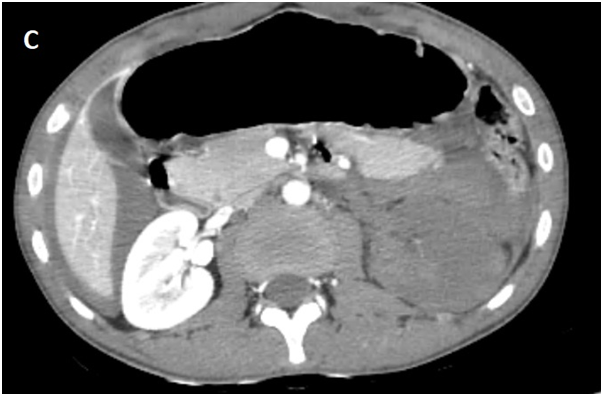

Whole body CT Scanner was performed 5hours after the accident Figure 1, which revealed a laceration fracture of the spleen responsible for a low abundant intraperitoneal hematoma, associated with left renal ischemia due to a sub intimal damage on the left renal artery wall, with formation of a secondary obstructive thrombus, in addition to a left peri-renal hematoma of 16mm, without parenchymal lesions or extravasation of contrast, otherwise ; left vein, the right kidney and his pedicle were intact.

Figure 1C Contrast enhanced CT abdominal scan.

laceration fracture of the spleen responsible for a low abundant intraperitoneal hematoma, associated with left renal ischemia due to a sub intimal damage on the left renal artery wall, with formation of a secondary obstructive thrombus, in addition to a left peri-renal hematoma of 16mm, without parenchymal lesions or extravasation of contrast, otherwise ; left vein, the right kidney and his pedicle were intact.